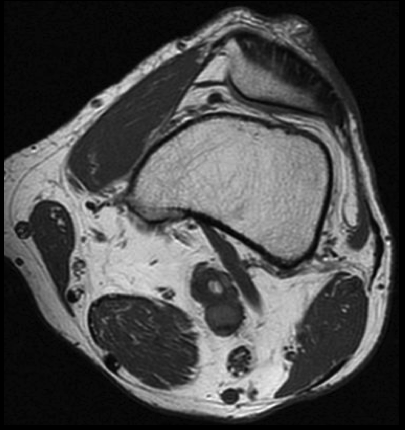

2. Tras analizar los cortes en planos axial y coronal, ¿cuál crees que es la causa de la obstrucción de la arteria poplítea izquierda?

- A. Ateroesclerosis.

- B. Enfermedad quística adventicial.

- C. Síndrome de atrapamiento poplíteo.

- D. Aneurisma trombosado.

- E. Enfermedad de Berger.

3. Para confirmar los hallazgos de la angioTC de extremidades inferiores, se realizó RM de rodilla izquierda. ¿Qué hallazgo se observa en la secuencia axial SE T1?